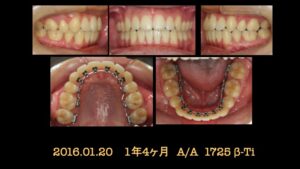

検査、診断の結果、上下顎前突と診断、上顎両側4番、下顎両側5番を抜歯し、患者さんの希望により、舌側矯正で治療を開始しました。

埋伏している 8番は抜歯を依頼しました。

治療開始から 1年 4ヶ月で抜歯空隙は既に閉鎖し、細部の仕上げに入ります。